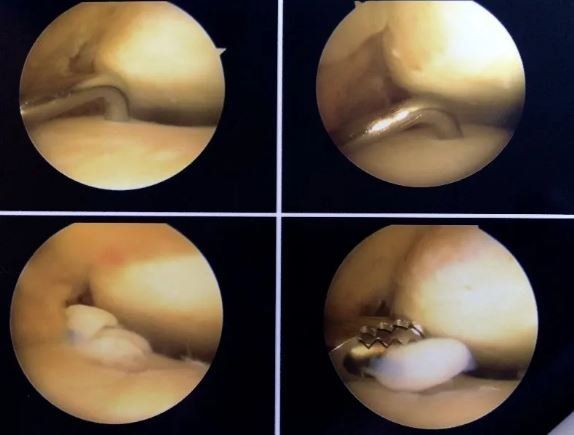

Difetto cartilagineo o difetto ostocondrale

Si tratta di aree localizzate con cartilagine e osso subcondrale (la porzione ossea al di sotto della cartilagine) danneggiate nell'articolazione della caviglia. I difetti osteocondrali sono di solito causati da lesioni alla caviglia, quali fratture e distorsioni. I sintomi più comuni includono dolore alla caviglia e gonfiore. I pazienti spesso lamentano blocchi e scricchiolii nella caviglia. La diagnosi viene realizzata utilizzando radiografie e risonanza magnetica. La TAC può essere utilizzata per valutare meglio eventuali lesioni che si approfondiscono nella porzione ossea. Il trattamento si basa sulla dimensione, posizione e stabilità del difetto osteocondrale. Solitamente la chirurgia consiste nell’asportazione della cartilagine danneggiata e nelle microperforazioni dell'osso nella sede di lesione per favorire la guarigione. Negli ultimi anni, si sono sviluppati substrati cartilaginei e scaffold artificiali che permettono la ricolonizzazione della cartilagine nella sede della lesione, dopo la sua bonifica.